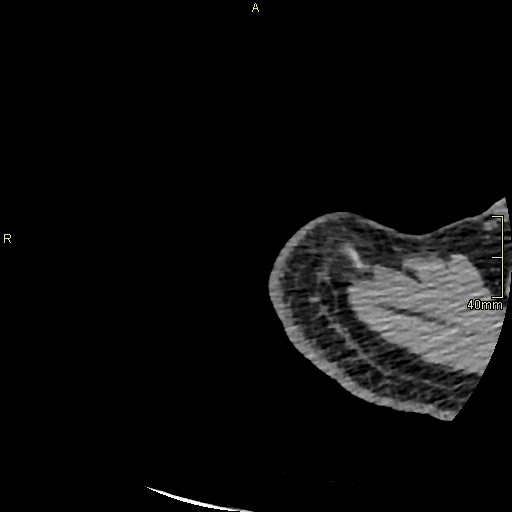

CT Humerus Contrast- Soft tissue window (axial)

CT Humerus Contrast- Bone window (axial)

CT Humerus Non Contrast- Bone window (axial)

CT Humerus Non Contrast- Soft tissue window (axial)